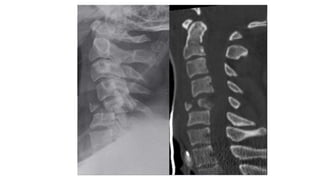

Rule of Spence

• #46 Soft tissue swelling Spinolaminar line c2 does not fall on the line Harris ring is a ring like structure resulting from proj of lat masses of c2 on its body. Ring disrupted Fat Body of c2 Thses could be the subtle radiolographic signs in hangman